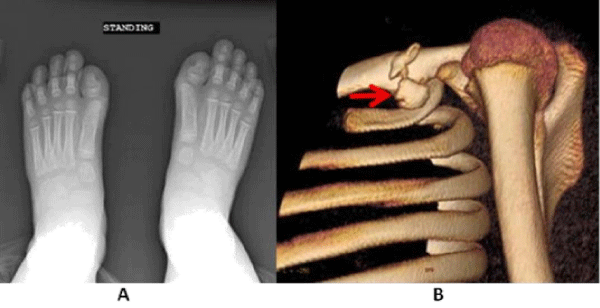

Figure 1: Case 1 - Fibrodysplasia Ossificans Progressiva. A: X-ray feet demonstrating Hallux Valgus deformity. B: 3D CT reconstruction noting a bony projection extending off of the anterior and inferior surface of the clavicle, at the junction of medial two third and lateral one third of the clavicle.